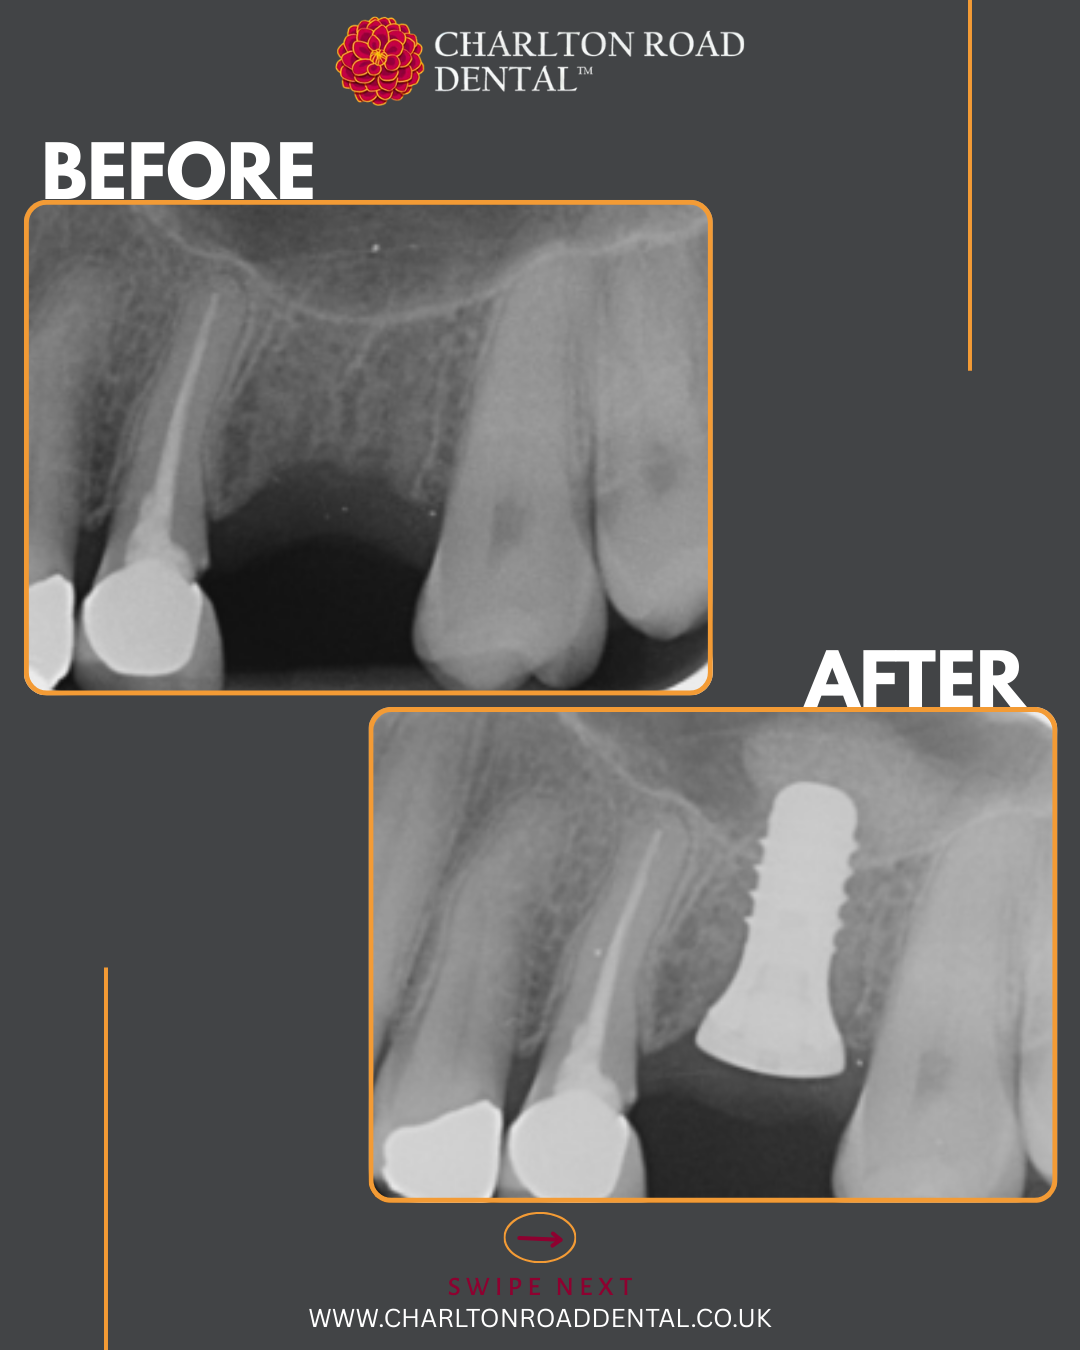

A week of implants @ Charlton Road Dental